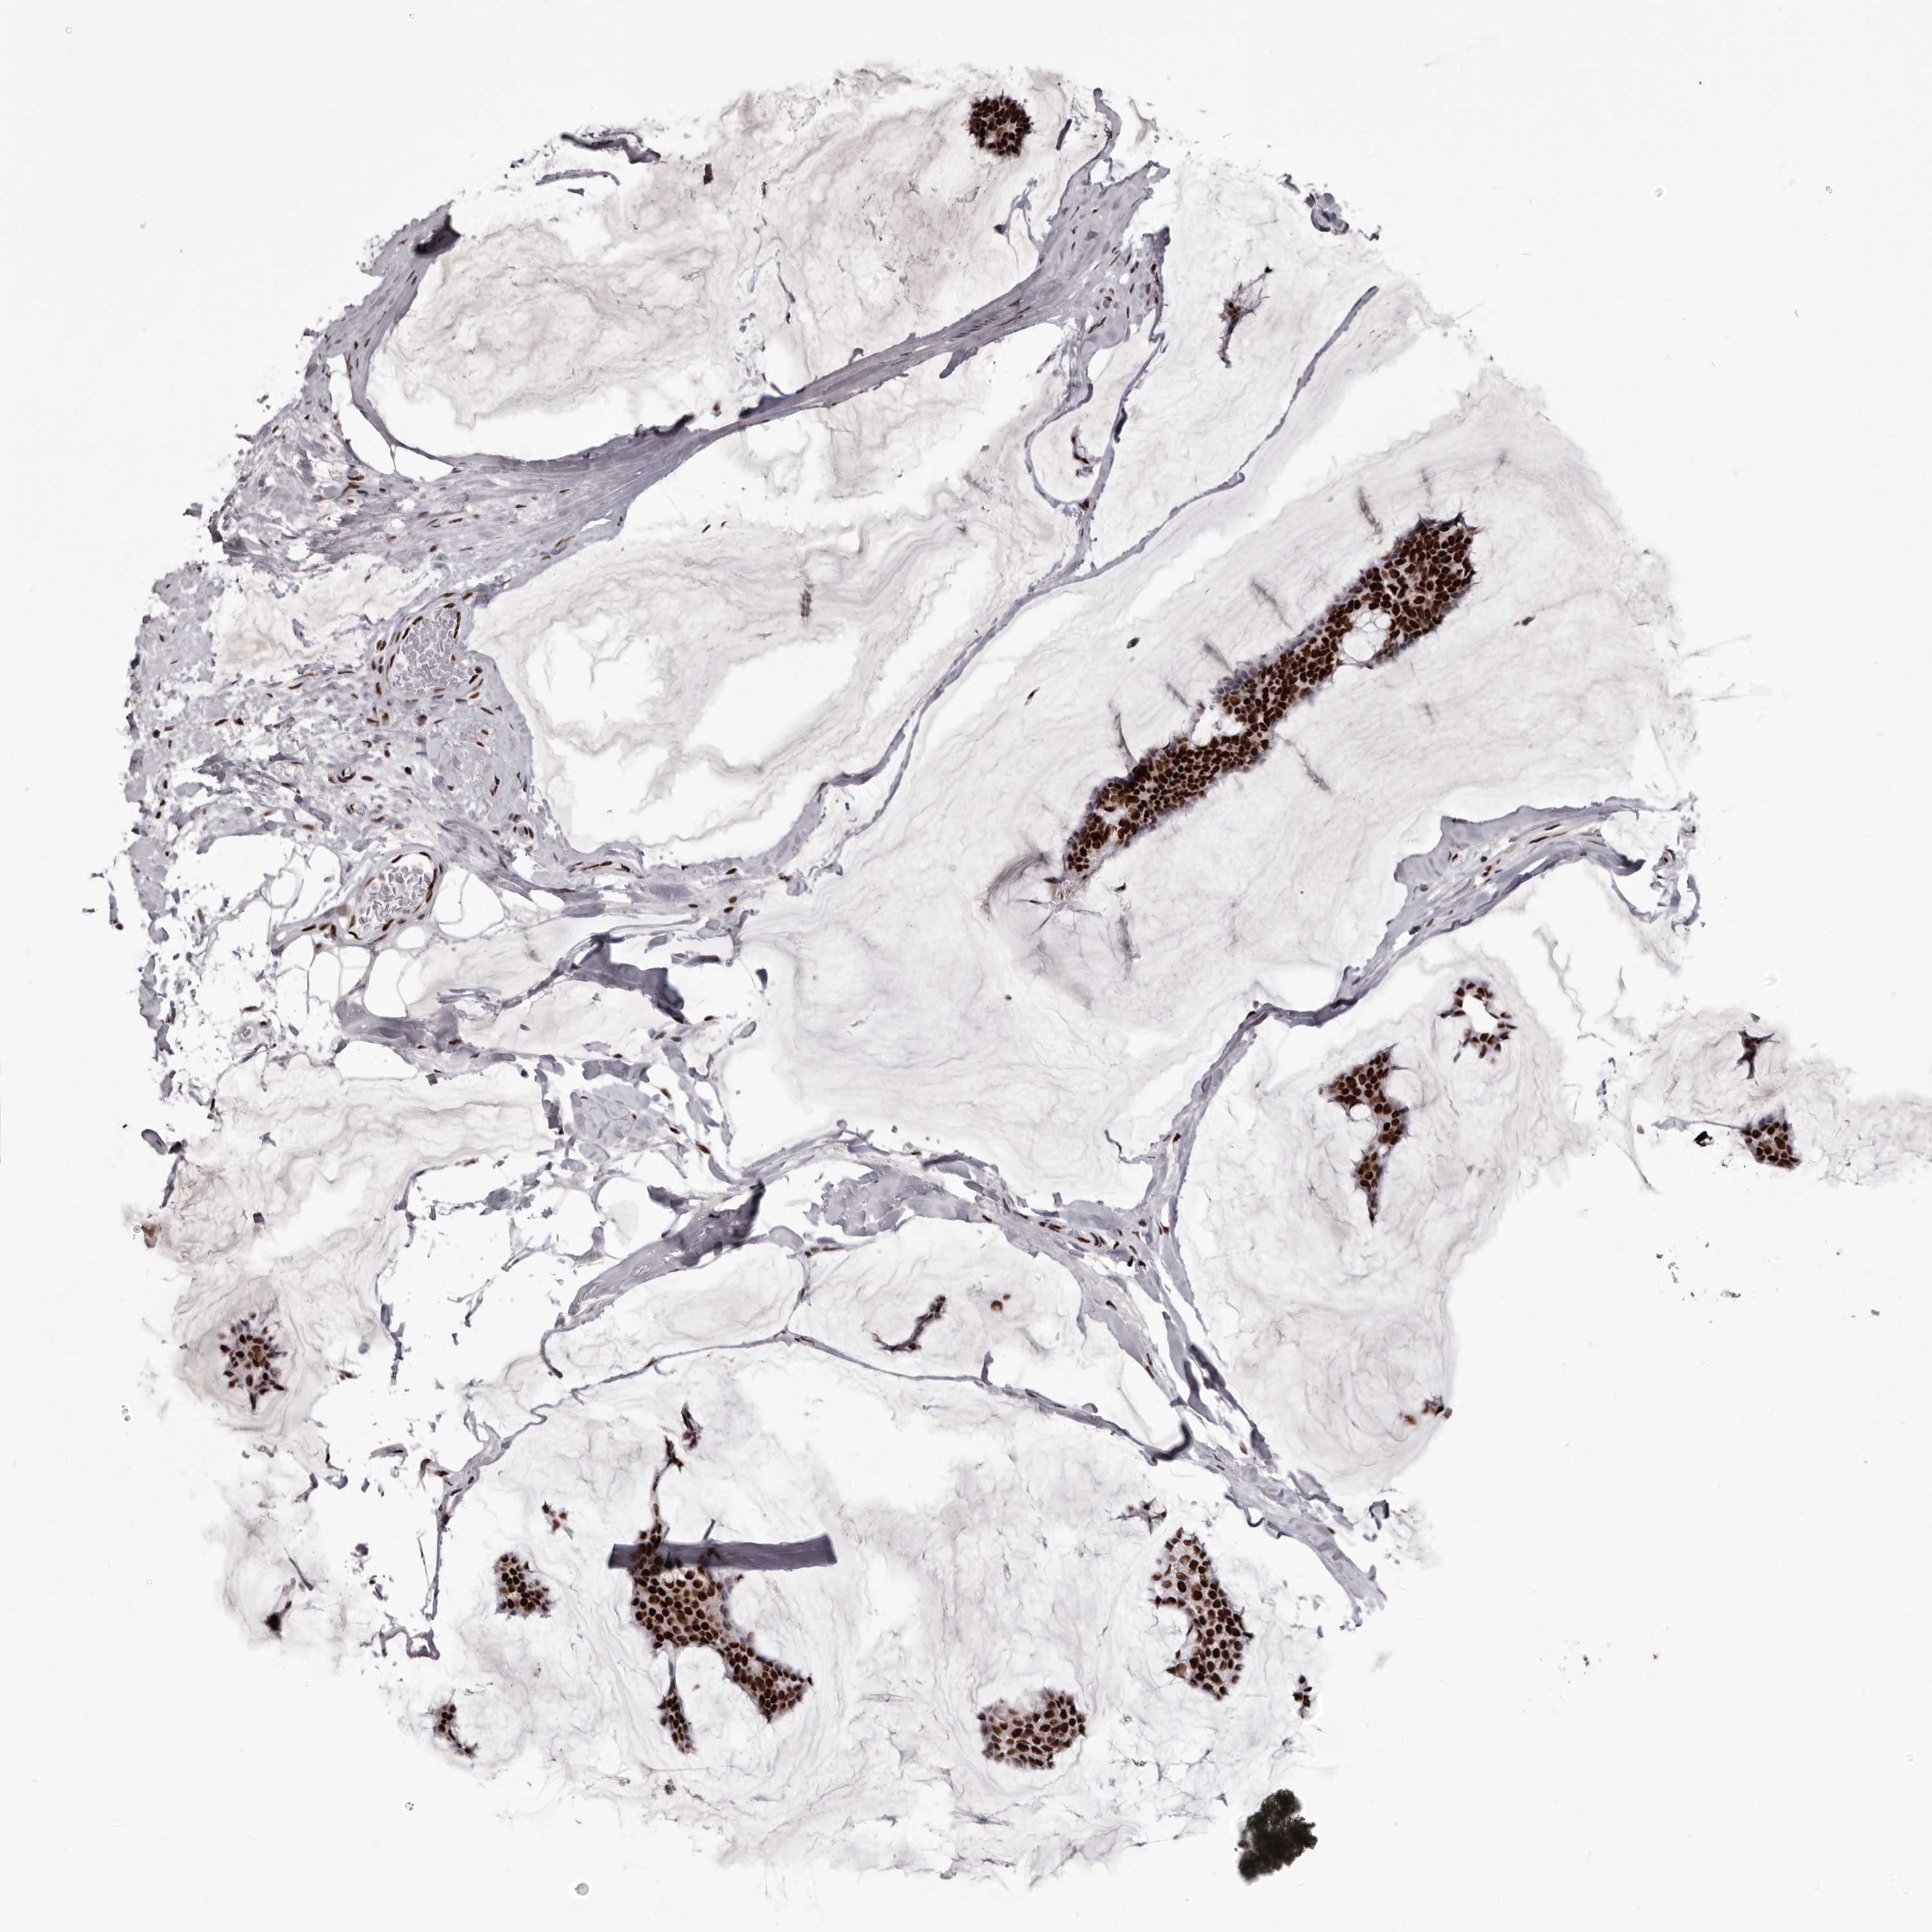

BRCA TCGA BRCA VALIDATION PROTEIN EXPRESSION

ANTIBODIES

AND

VALIDATION